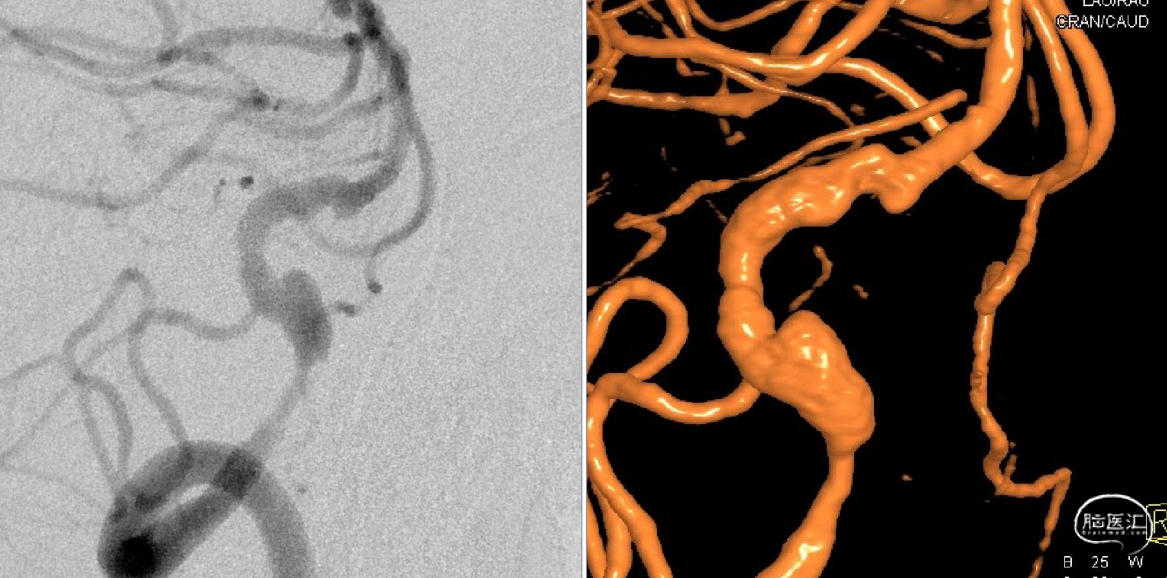

主动脉弓置换术后颅内动脉瘤的治疗

材料:6F 桡动脉穿刺鞘、5F Envoy造影管、Simmon1-2造影管,0.035inch微导丝

股动脉入路造影困难,难以进入主动脉弓

双侧颈总动脉、右侧椎动脉造影

Simmon1 成型(猪尾巴支撑差,无法完成)

动脉瘤大小:4.35mm*2.83mm